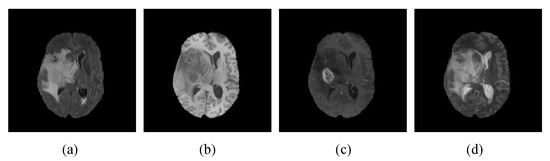

4.1. Datasets and Evaluation Indicators